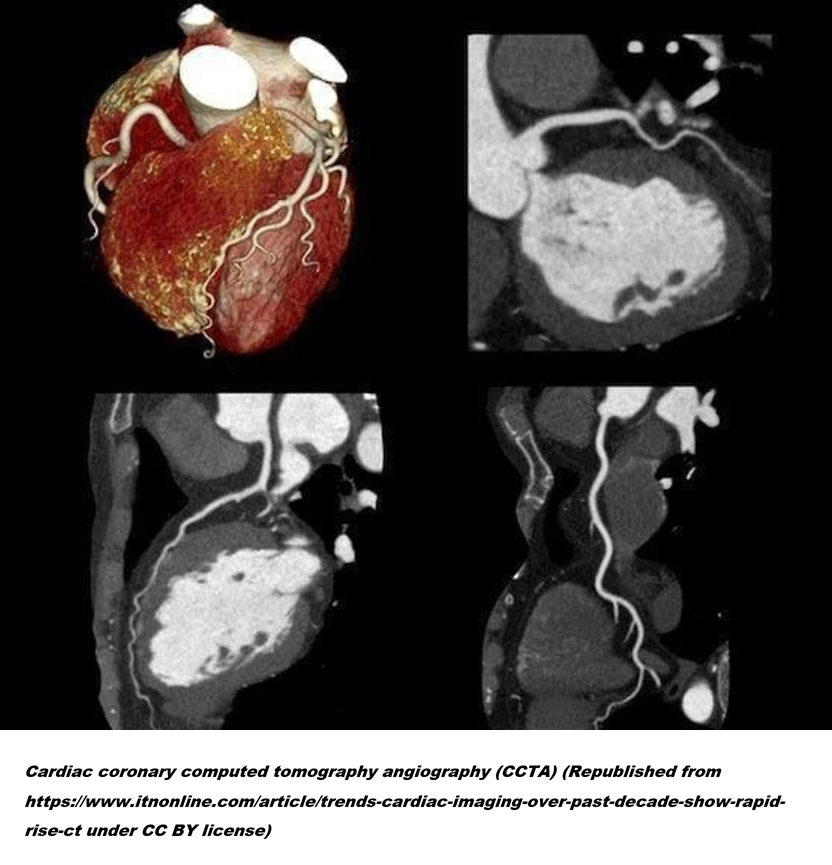

3. 관상동맥 CT 혈관조영술(Coronary Computed Tomography Angiography, CCTA)은 조영제를 사용하여 관상동맥의 혈관 상태를 시각화해 주는 검사입니다. 이 검사를 통해 우리는 관상동맥의 협착 정도뿐 아니라, 나아가서는 경화반의 성상(취약도)까지 짐작할 수 있습니다. 연구를 통해 CCTA 검사는 환자에게 추가적인 관상동맥 조영술 검사가 필요할지를 알려주고, 치료 전략을 수립하는 데 큰 도움이 된다는 것이 증명되었습니다.

6. 이러한 상황에서 근본적인 치료는 혈류를 회복시켜 주는 것입니다. 즉, 사고 발생 너머 조직에 산소를 다시 전달하기 위해 막힌 혈관을 뚫어줍니다. 막혀버린 수도관을 시원하게 뚫어주면 그간 빗물을 받아 쓰며 근근이 버티던 마을 사람들이 다시 일상을 회복할 수 있는 것과 같은 이치입니다. 의사들은 관상동맥에 접근해 풍선으로 직경을 넓히고 넓혀진 관에 금속 망(스텐트)을 넣어 관류량을 회복시킵니다.

7. 한데 이 ‘막힌 관상동맥을 뚫어준다’는 게 말은 매우 쉬울지 몰라도 실제로는 극히 위험하고 복잡하며 침습적이라는 것이 문제입니다. 정말 막힌 게 맞는지 확인만 하는 것도 큰 마음을 먹고 시작해야 합니다. 그도 그럴 것이 심장은 한시도 멈춰있지 않고 언제나 움직이는 장기이며, 시술 중 심장이 멈추게 될 경우 즉시 생명이 위협받을 수 있습니다. 더구나 관상동맥에 접근하기 위해서는 필히 대동맥을 거슬러 올라 심장까지 역으로 접근해야 하는 점도 문제였습니다.